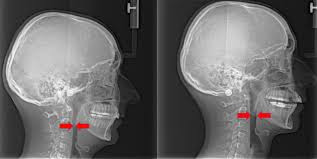

Mewing Posisi Lidah Bisa Membuatmu Lebih Menarik Kaskus